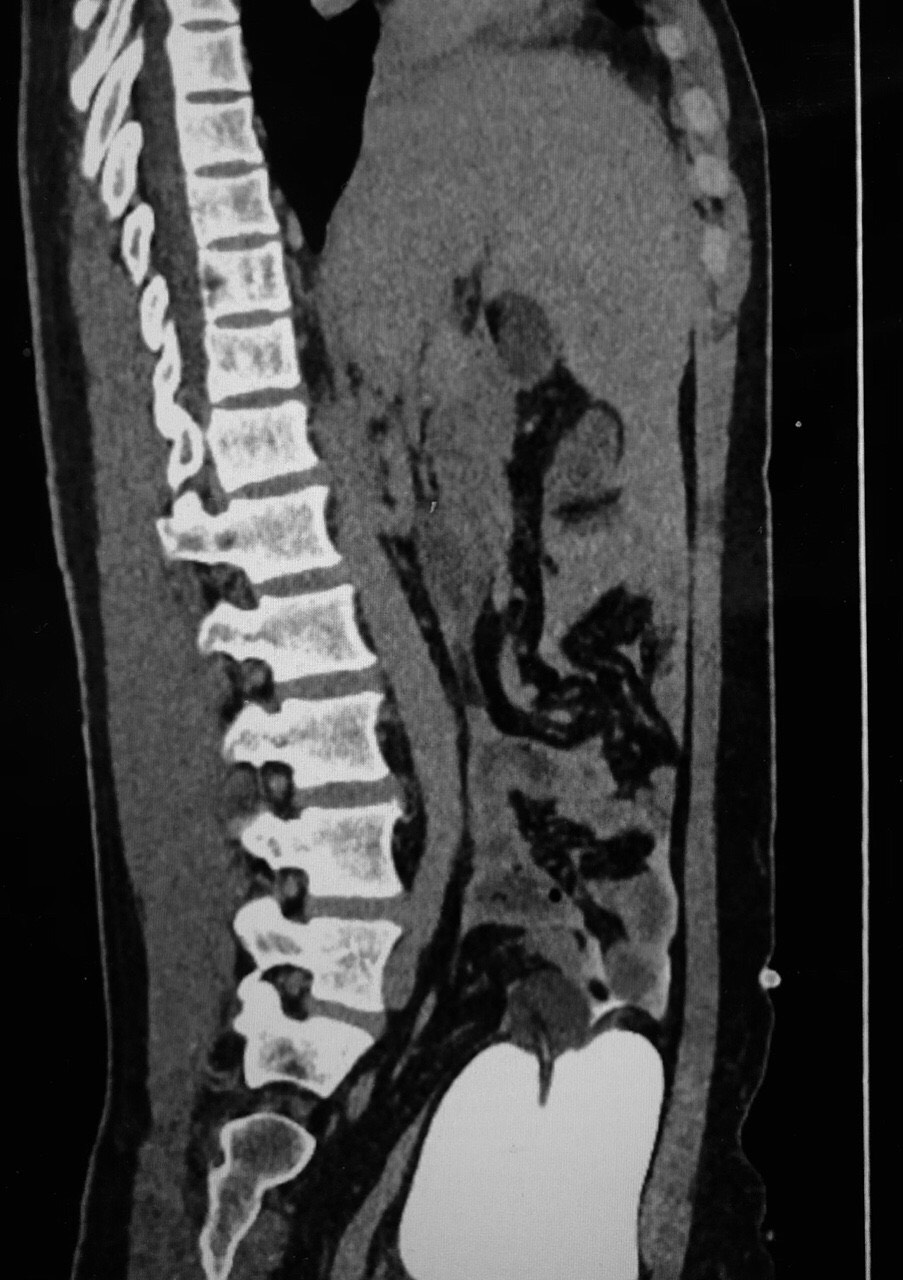

Hình ảnh chụp CT của bệnh nhân T